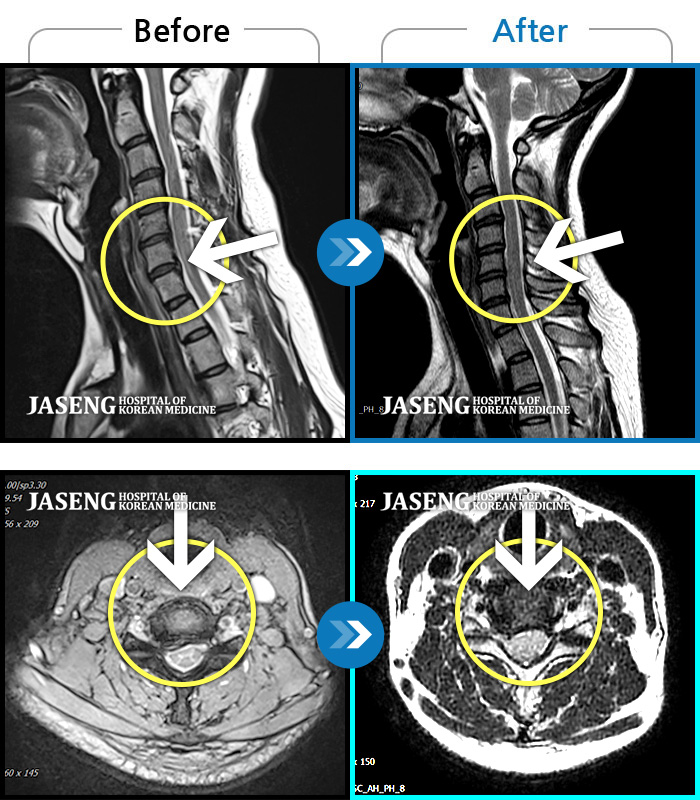

처음 내원시 목에서 등으로 이어지는 통증 및 우측 팔 저림 증상이 심했고, 약간의 근력저하도 동반되어 일상생활이 어려운 상태였습니다. |

[인천] 24.04.06~24.11.16

※ 환자분에게 사전 동의를 받아 동일 조건에서 촬영되었으며, 개인에 따라 치료 후 부작용이 발생할 수도 있으니 사전에 의료진과 상담 후 치료를 진행하시기 바랍니다.